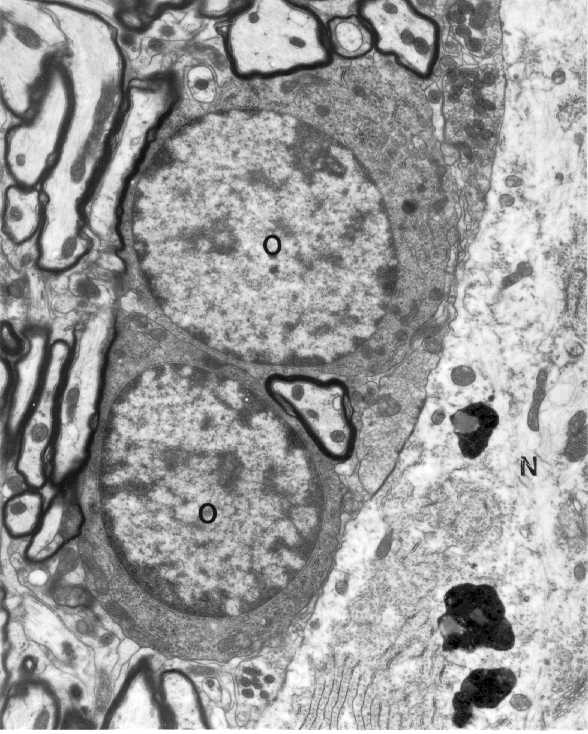

Two oligodendrocytes(o) of the dark type in close apposition to the cell

body of a neuron(N). The nucleus conntains clumps of chromatin materials

Can you recognize any axon terminals forming synaptic contacts with the

neuron? Profiles of myelinated axons are seen on the left of the figure.